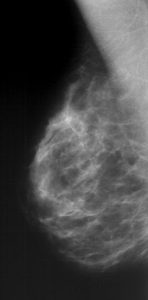

Jedná se o rentgenové vyšetření prsu za účelem odhalení počátku rakovinného bujení. Je základní zobrazovací metodou u většiny žen. Zpravidla se nehodí pro ženy mladé, u kterých je žláza bohatá a hutná. Mamografie se provádí na přístroji, mamografu, který využívá tzv. měkké rentgenové záření. Při vyšetření se prs musí dostatečně stlačit, je to nutné pro dosažení vysoké kvality snímku. Obvykle se vyšetřuje prs ve dvou rovinách, celkem se tedy provádí 4 snímky.

Některá mamografická vyšetření je nutno ještě doplnit ultrazvukovou kontrolou. Na našem pracovišti je toto vyšetření prováděno bezprostředně v týž den, v rámci jedné návštěvy pacientky. U plánovaného vyšetření je optimální vyšetřovat v první polovině menstruačního cyklu, kdy je možné prsy dostatečně stlačit bez nepříjemných pocitů vyšetřované ženy, při nebezpečí z prodlení (při podezření na zhoubný nádor ) se nečeká.Co je mamografický screening?

Mamografický screening znamená pravidelné preventivní vyšetřování žen bez jakýchkoliv příznaků onemocnění s cílem zachytit rozvíjející se onemocnění v co nejčasnějším stadiu. Princip fungování mamografického screeningu vychází z předpokladu, že onemocnění zachycené v časné fázi je snáze léčitelné a vede k vyšší kvalitě a vyšší délce života pacientek.

Diagnostická mamografie – se provádí u pacientů s příznaky zhoubného onemocnění prsu nebo u již diagnostikovaného zhoubného onemocnění prsu nebo jako doplňující vyšetření ke screeningové mamografii.

Screeningová mamografie – je prováděna v souladu s příslušnou vyhláškou MZ ČR v rámci preventivních prohlídek a dispenzární péče. Není vhodnou metodou pro ženy mladší 40 let (s výjimkou žen s výrazně zvýšeným rizikem vzniku karcinomu prsu, které jsou sledovány podle individuálně určeného schématu) a neměla by být prováděna častěji než každoročně. K vyšetření přichází žena do screeningového mamografického centra se žádankou k provedení tohoto výkonu nebo s pozvánkou (indikace na základě věku). Žena-samoplátkyně se může k vyšetření dostavit přímo na pracoviště bez příslušné žádanky.Duktografie – je indikována u pacientů se spontánní patologickou sekrecí z bradavky, která by mohla být projevem nádorového onemocnění (papilom, karcinom aj.) . Do secernujícího mlékovodu je vpravena kontrastní látka a následně provedeny snímky.

Přístrojové vybavení a ukázkové snímky:

- Mammomat Inspiration, Siemens